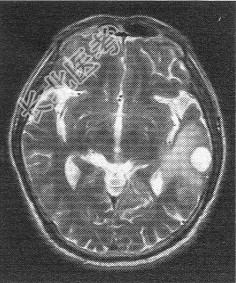

- 单项选择题患者男,72岁。肺癌术后一年余, 现出现头晕头痛,MR图像如下, 最具有可能的诊断是

B、脑转移癌